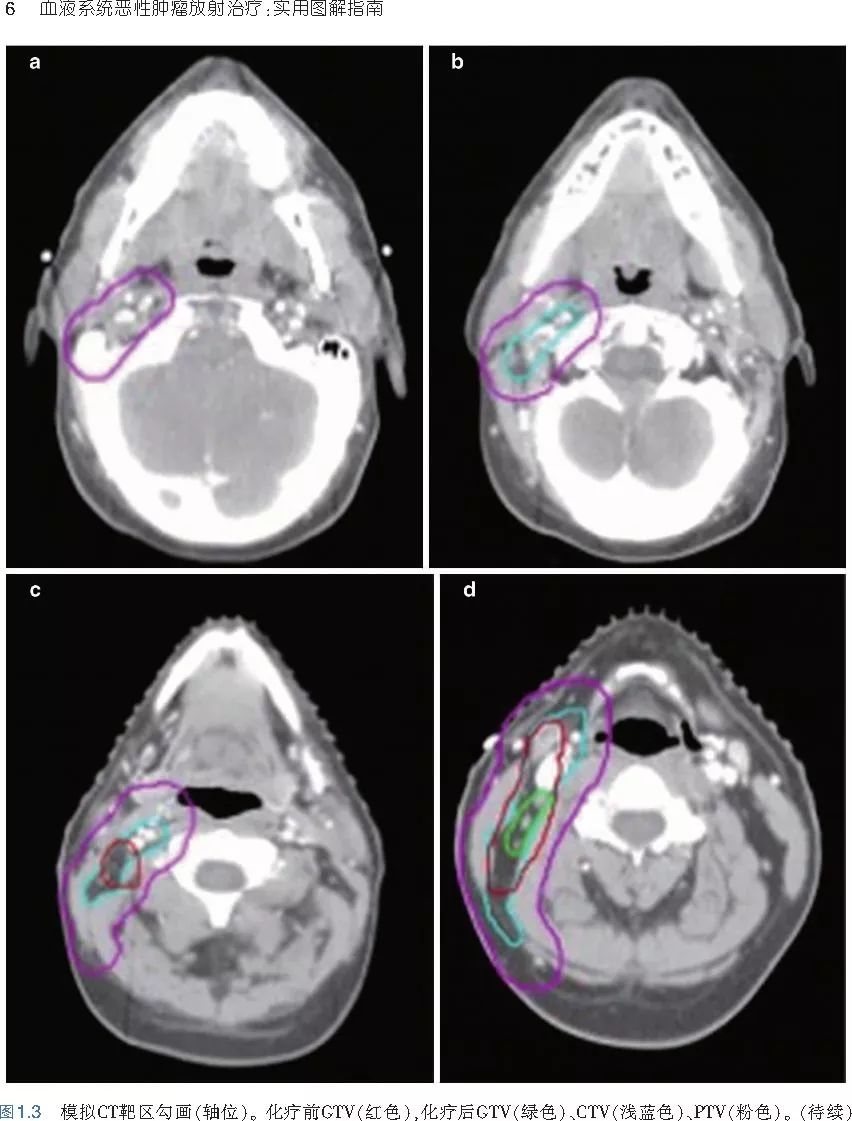

❤ 展开疾病诊断、病理描述及治疗方向的详细阐述,包含医学影像,图文并茂,深入浅出。

本书旨在帮助临床医生对常见血液系统恶性肿瘤疑难病例进行管理,包括霍奇金淋巴瘤、非霍奇金淋巴瘤和白血病患者,并通过多个病例进行阐述。案例讨论遵循标准格式,包括临床描述,其次是与诊断相关的病理描述和分期,然后详细讨论治疗选择。最后,确定治疗方案,并提供所使用的规划放疗技术/方式的图像。对放射肿瘤医生进行临床决策非常有帮助,对于血液病临床医生也有很好的指导作用。